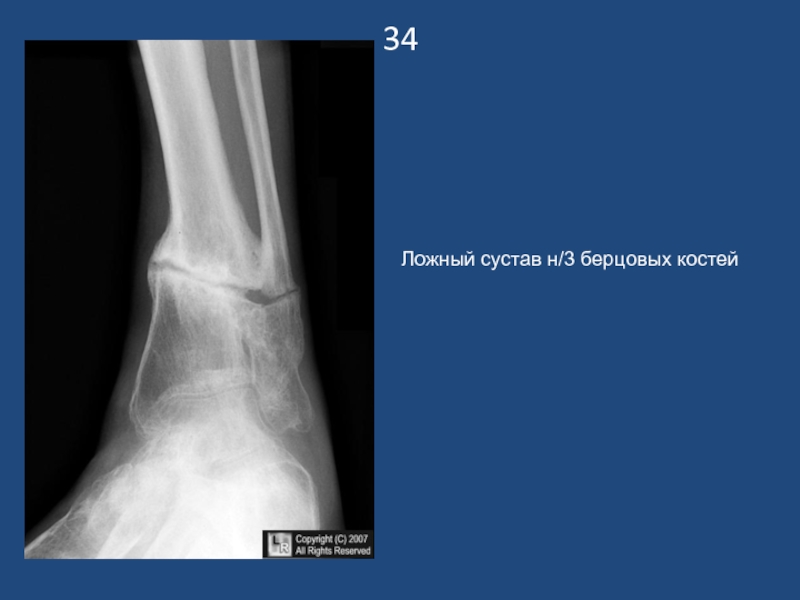

Слайд 3534

Ложный сустав н/3 берцовых костей